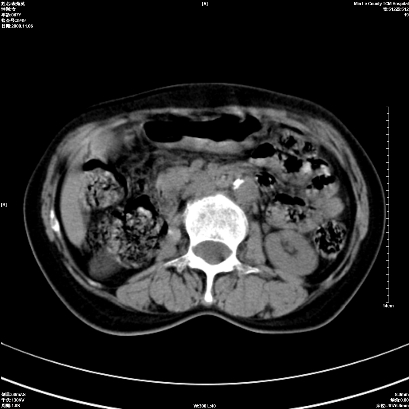

以下是引用卜一在2008-11-6 15:58:00的发言:[br]胰头略增大,胆总管扩张,末端渐行性狭窄。多考虑:胰头癌!建议增强!

以下是引用huangyinshan在2008-11-6 16:32:00的发言:[br]胰头略增大,胆总管扩张,末端渐行性狭窄。多考虑:胰头癌!建议增强!